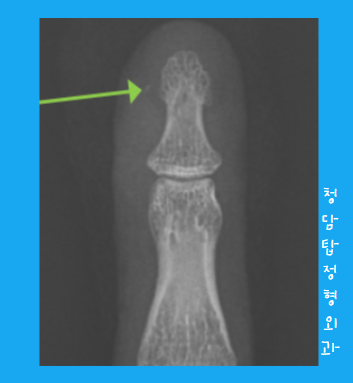

이 과정이 끝나면, 다시 엑스레이를 찍어 제거가 여부를 다시 확인을 합니다.

찍어보니, 숨어있던 파편이 보이네....요??

다시 시작해 볼까요?